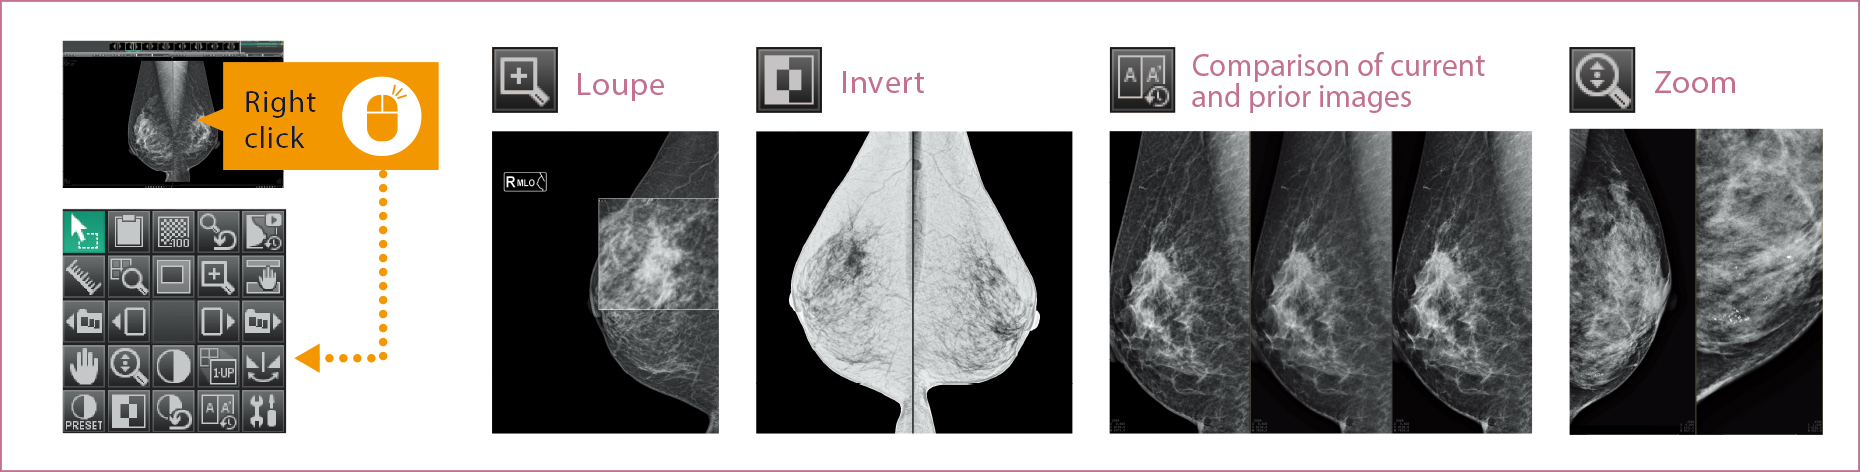

Support for users in conducting diagnosis with reading protocols tailored to mammographic diagnosis and smooth image displays. Customization for reading protocols includes configuration for making comparisons of current and prior images and for S-views synthesized from tomosynthesized images of AMULET Innovality and AMULET SOPHINITY.